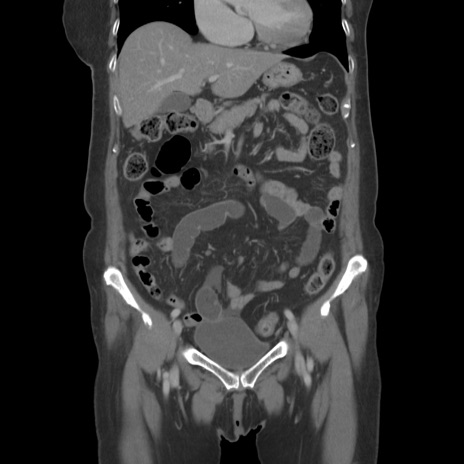

症例19(冠状断像)

【症例】80歳代女性

【主訴】下腹部痛

【現病歴】約8時間前より下腹部痛の出現あり、救急外来受診。

【既往歴】両側付属器切除

【身体所見】意識清明、下腹部正中に手術痕あり、その部位に一致して圧痛と反跳痛あり。腸蠕動音は亢進。

【データ】WBC 9300、CRP 0.15